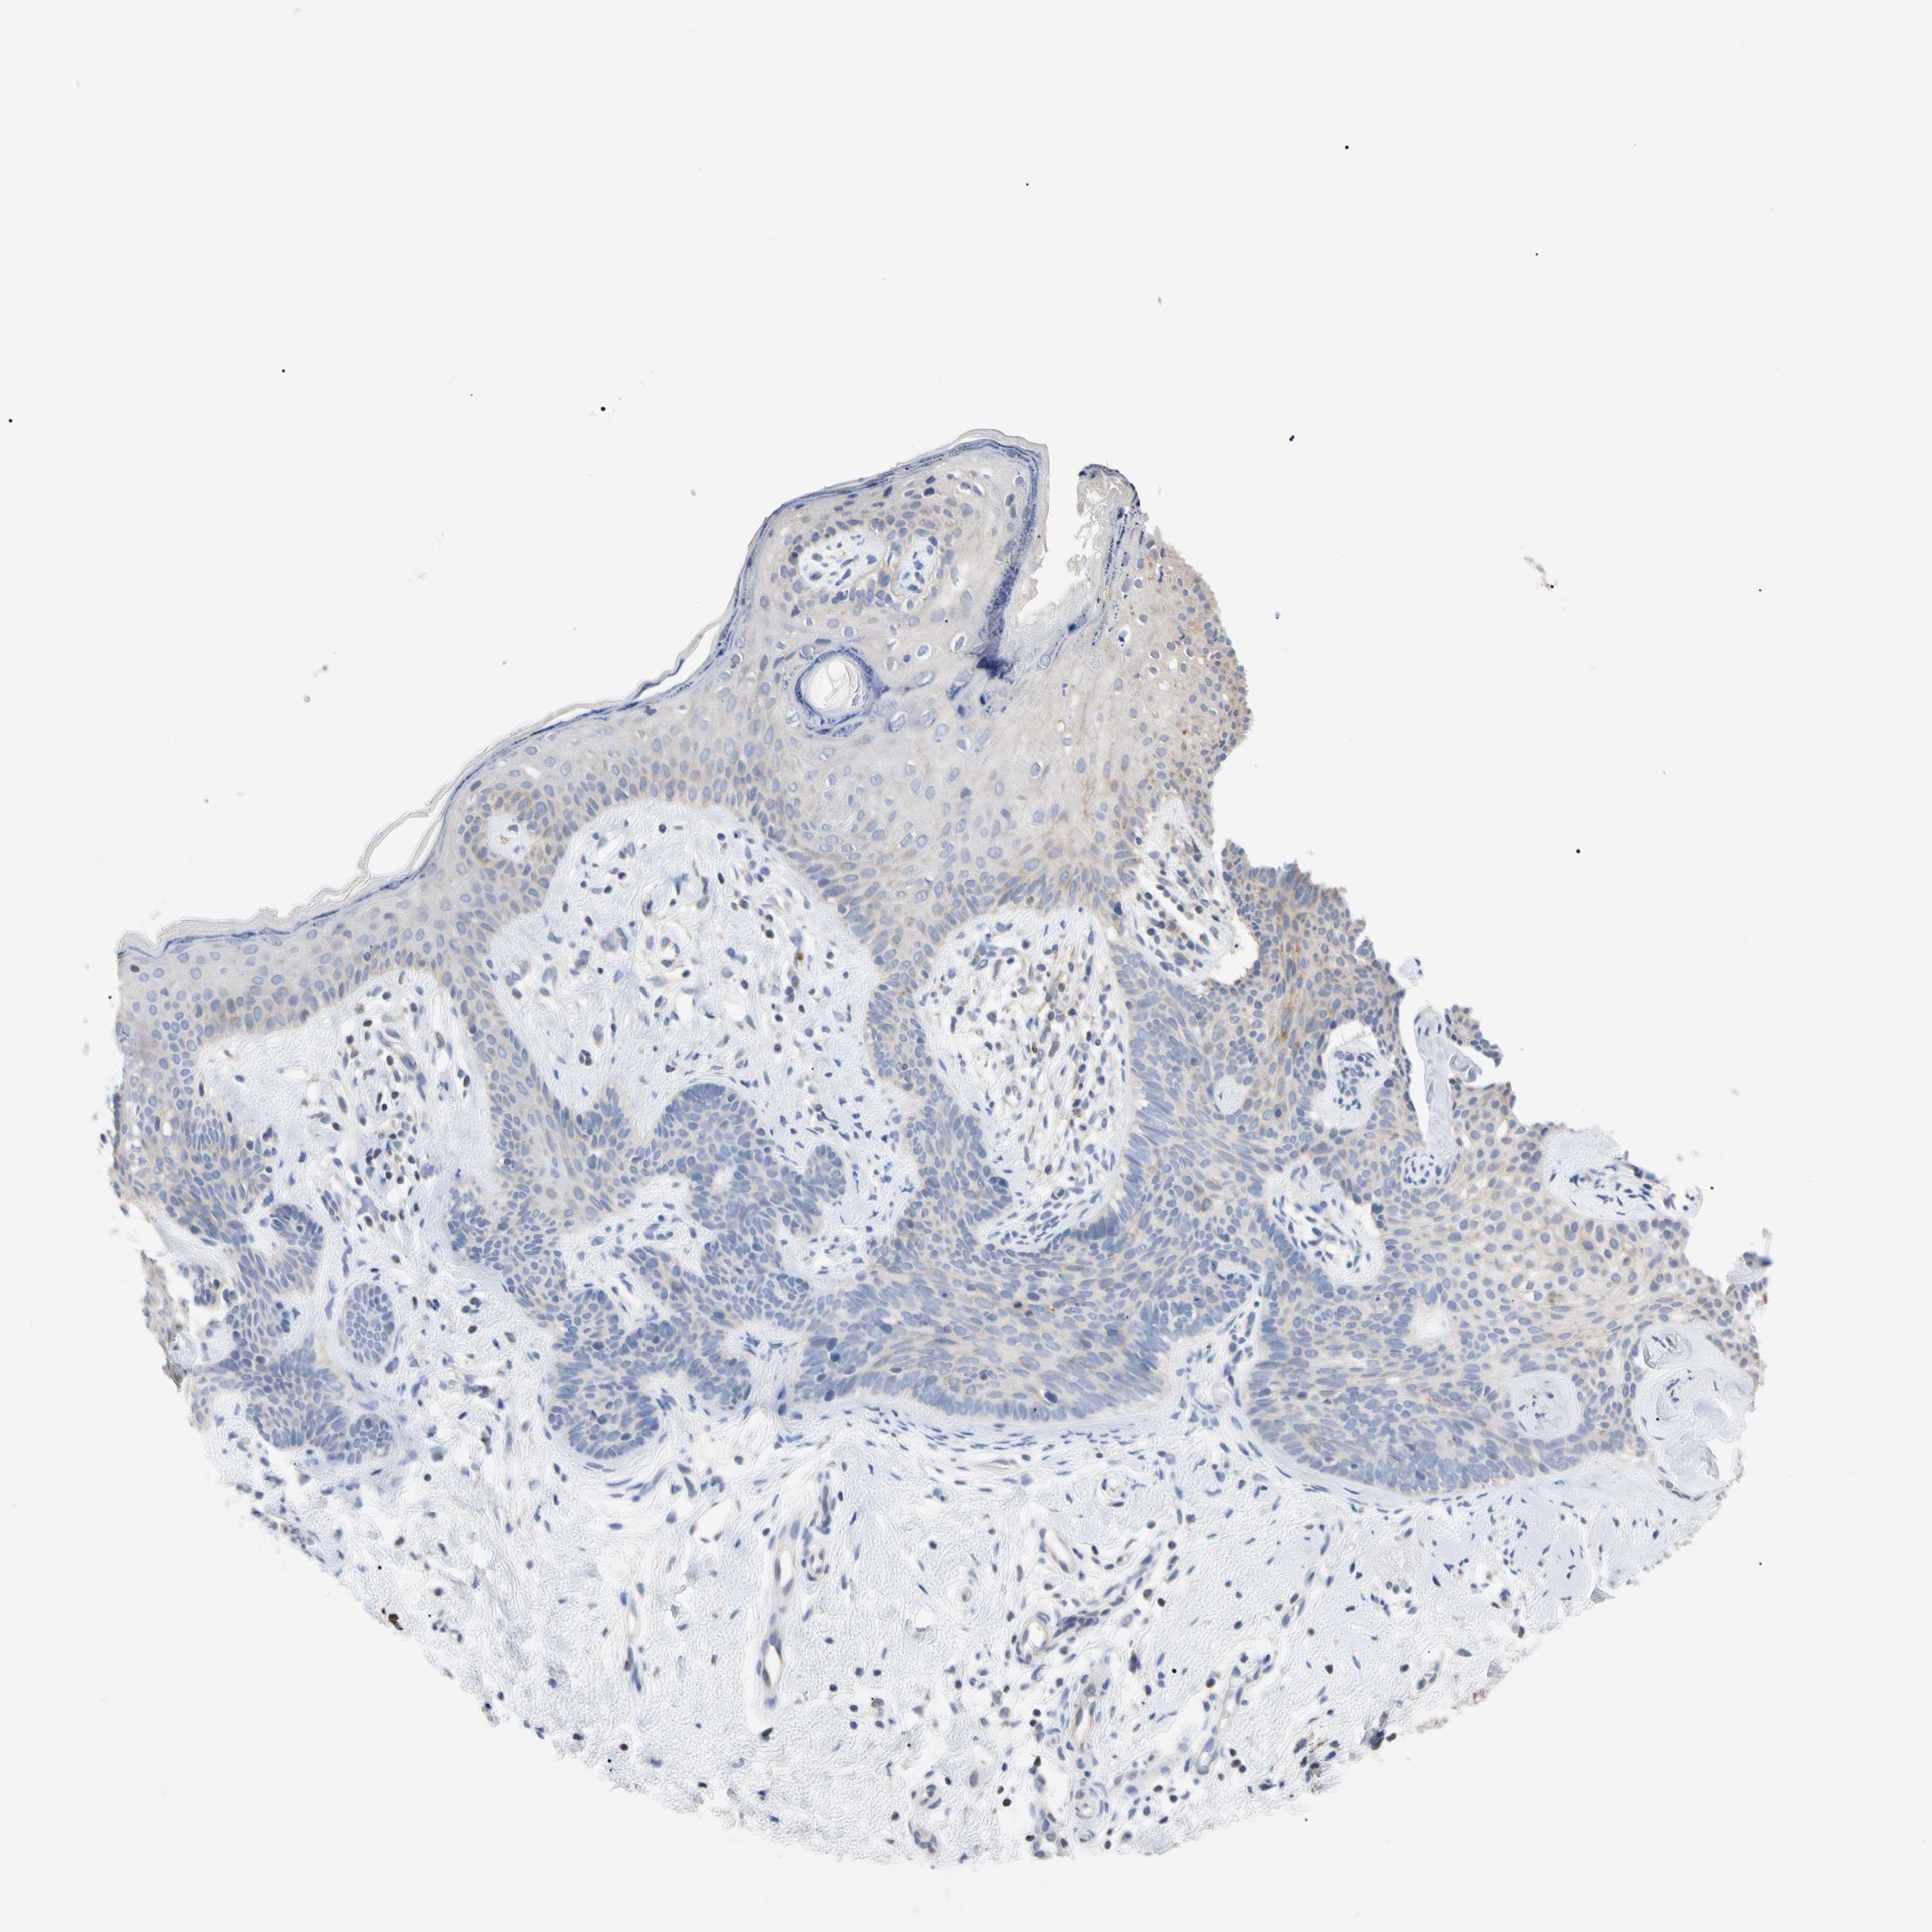

SKIN CANCER - Protein expressioni

A mouse-over function shows sample information and annotation data. Click on an image to view it in a full screen mode. Samples can be filtered based on level of antibody staining by selecting one or several of the following categories: high, medium, low and not detected. The assay and annotation is described here.

Antibody stainingi

Antibody staining in the annotated cell types in the current human tissue is reported as not detected, low, medium, or high, based on conventional immunohistochemistry profiling in selected tissues. This score is based on the combination of the staining intensity and fraction of stained cells.

Each image is clickable and will lead to virtual microscopy that enables deeper exploration of all samples and also displays staining intensity scores, fraction scores and subcellular localization as well as patient and tissue information for each sample.

Antibody HPA008455

Antibody HPA031125

Antibody CAB002781

Antibody CAB068195

Squamous cell carcinoma, NOS

Squamous cell carcinoma, metastatic, NOS

Basal cell carcinoma

Papilloma, NOS